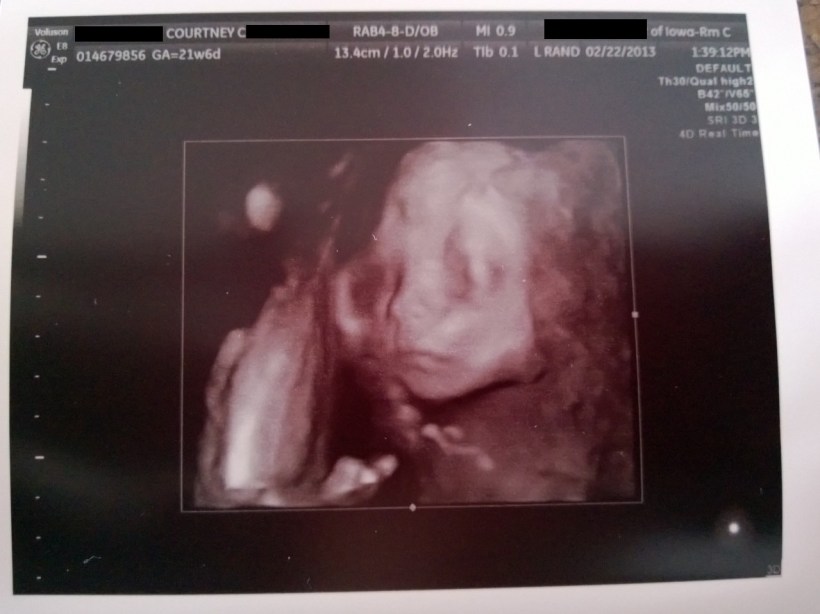

Here is Wilson, looking cute and HEALTHY!